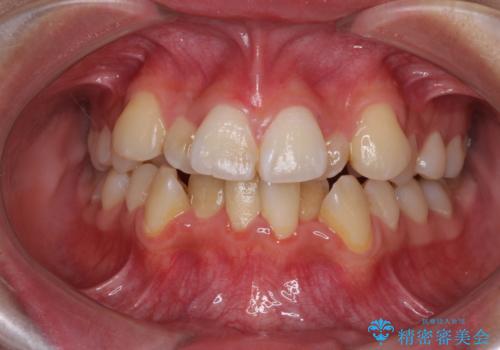

- 上下前歯のデコボコと、それによる磨きづらさを気にして来院された患者様です。

叢生解消のため、上下左右第一小臼歯4本を抜歯し、ワイヤー装置にて矯正治療を行うこととしました。